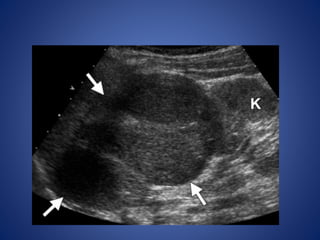

• #42 ACN in a 23-month-old girl with virilization. (a) Longitudinal US image shows a large, lobulated adrenal mass (arrows) above the kidney